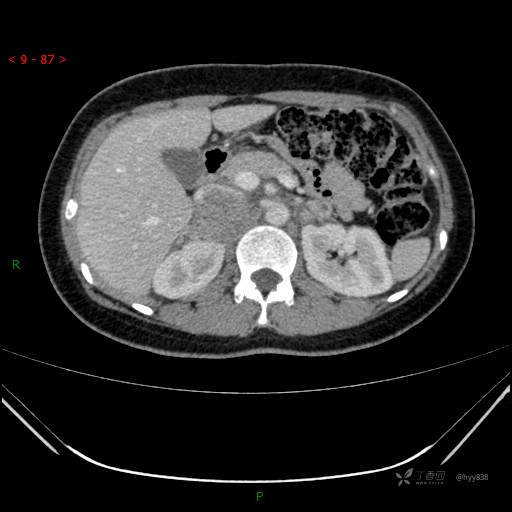

辅助检查:CT

静脉期